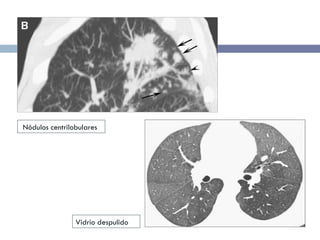

Otros signos radiológicos Nódulos centrilobulares (50%) Opacidades lineales irregulares 1 o más nódulos mayores de 3 cm (Opacidades grandes redondeadas) DP moderado

TCAR Micronódulos centrilobulares de baja densidad (3-5 mm)  Opacidades de vidrio deslustrado Engrosamiento de la pared bronquial Enfisema centrilobular (50%)

TCAR Micronódulos centrilobularesde baja densidad (3-5 mm) Opacidades de vidrio deslustrado Engrosamiento de la pared bronquial Enfisema centrilobular (50%)

• #38 High-resolution CT image of the upper lung lobes shows centrilobular nodules (white arrows) and patchy ground-glass opacities (black arrow). Mild coexisting centrilobular emphysema is seen (cabeza de flecha)